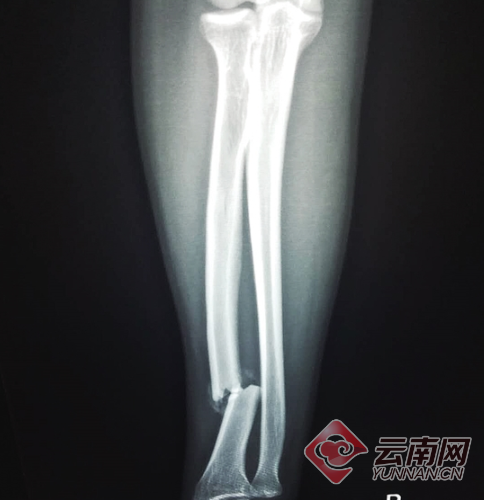

“带我去医院吧。”面对小伙的要求,驾驶员开车将其送到西山区人民医院。照了胸片和CT,CT结果显示伤者右手桡骨骨折。